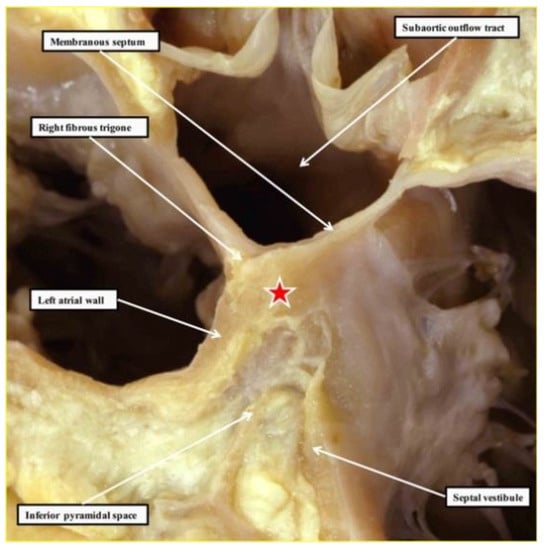

2. The Location and Architecture of the Normal Atrioventricular Conduction Axis

2.1. The Structure of the Normal Atrioventricular Junctions

2.2. Location of the Atrioventricular Node

2.3. Penetration and Branching of the Conduction Axis